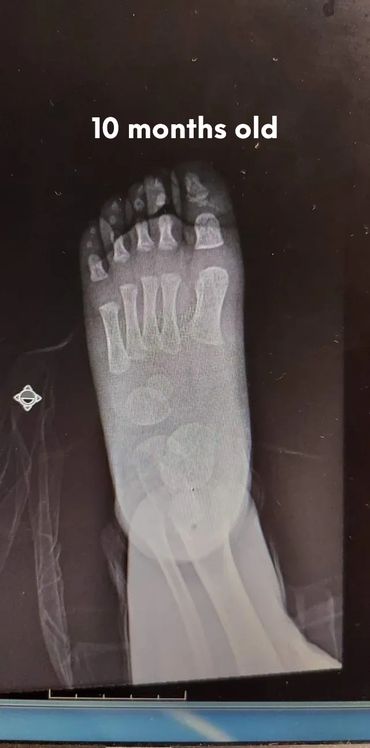

Babies’ feet are very soft and mostly made of cartilage in the first years of life. Their bones are still forming, and they have a thick layer of fat that makes their feet look chubby. This is why it’s important not to restrict their feet with tight or rigid shoes, as it could affect the natural shape and growth.

Let's check what their foot bones look like.

Pictures below will let you understand how babies' feet are developed.

Dear parents, children’s feet are developing structures, and the absence of an arch is a typical stage of development. The developing foot is not structurally ‘flat’; it is a highly compliant and plastic, that can respond to multiple factors, many of which we do not understand. Detailed X-RAY pictures above, let us understand that babies' foot bones are not connected till the teen years. Only at the age of 14, we may consider that the bones in the feet are developed and have reached their connections.